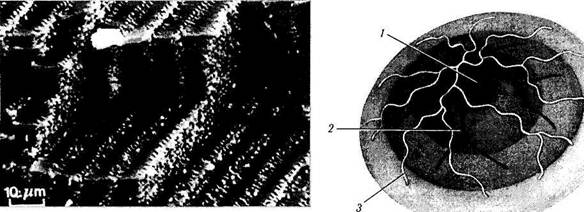

При биомикроскопическом исследовании хрусталика с расширенным зрачком можно обнаружить особенности его структурной организации (рис. 3.4.3). Во-первых, выявляется мно-гослойность хрусталика. Различаются следующие слои, считая спереди к центру: капсула; подкапсулярная светлая зона (кортикальная зона С 1а); светлая узкая зона неоднородного рассеивания (С1); полупрозрачная зона коры (С2). Перечисленные зоны и составляют поверхностную кору хрусталика. Существует еще две более глубоко расположенные зоны коры. Их называют еще пернуклеарными. Эти зоны флюоресцируют при освещении хрусталика синим светом (СЗ и С4).

а 6 6

Рис. 3.4.3. Послойность строения хрусталика при биомикроскопическом его исследовании у индивидуумов различного возраста (по Bron et al., 1998):

а — возраст 20 лет; б — возраст 50 лет; s — возраст 80 лет (/ — капсула; 2 — первая кортикальная светлая зона (С1 альфа); 3 — первая зона разобщения (С1 бета); 4 — вторая кортикальная светлая зона (С2): 5 — рассеивающая свет зона глубокой коры (СЗ); 6 — светлая зона глубокой коры; 7 — ядро хрусталика. Отмечается увеличение хрусталика и усиление рассеивания света

Ядро хрусталика рассматривают как его пре-натальную часть. Оно также обладает слоистостью. В центре располагается светлая зона, называемая «зародышевым» (эмбриональным) ядром. При исследовании хрусталика с помощью щелевой лампы также можно обнаружить швы хрусталика. Зеркальная микроскопия при большой кратности увеличения позволяет увидеть эпителиальные клетки и волокна хрусталика.